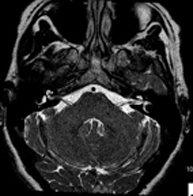

- RM Cerebral (craneal)

Prueba diagnóstica no invasiva que consiste en la obtención de imágenes de alta definición anatómica del cerebro mediante el empleo de un campo electromagnético y ondas de radio (con un emisor y un receptor). No utiliza radiación ionizante. Indicaciones: problemas vasculares, pérdida de memoria, epilepsia, cefalea, malformaciones, sospecha de tumor, meningitis. - RM Cais

Prueba diagnóstica no invasiva que consiste en la obtención de imágenes de alta definición anatómica de las arterias cerebrales mediante el empleo de un campo electromagnético y ondas de radio (con un emisor y un receptor). No utiliza radiación ionizante. En la mayoría de los casos es necesario el empleo de contraste paramagnético (Gadolinio). Permite un estudio angiográfico no invasivo gracias a la inyección de Gadolinio con posterior reconstrucción en 2D y 3D, gracias a estaciones de trabajo especializadas. Indicaciones: malformaciones vasculares, aneurismas de arterias cerebrales, arteriosclerosis. - Angio-RM troncos supraaórticos